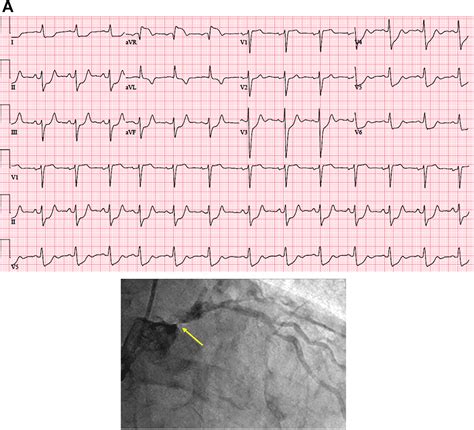

• Electrocardiogram (ECG): This test records the electrical activity of the heart and can detect abnormalities indicative of a heart attack.

• Coronary angiography: This procedure involves inserting a catheter into the heart to visualize the coronary arteries and identify blockages.